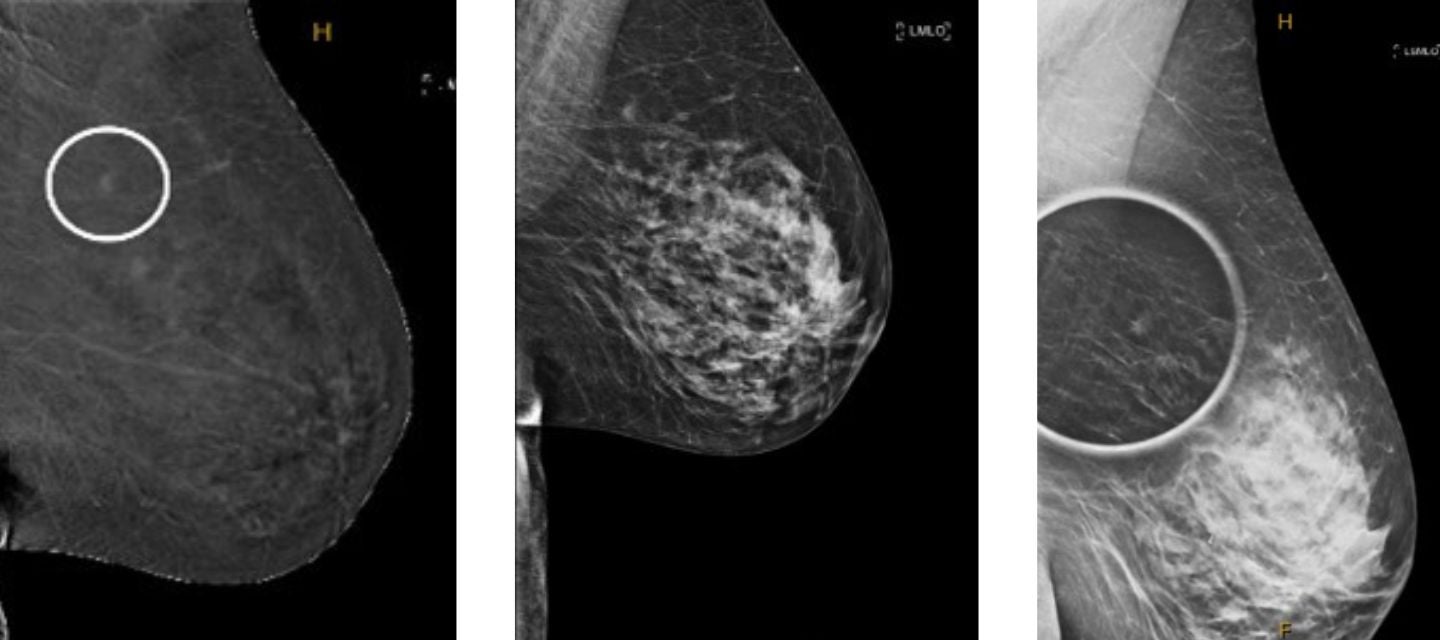

CEM works by combining standard mammography with an iodine-based contrast agent providing more detailed imaging of the breast's vasculature.

Due to its sensitivity, CEM can be particularly valuable for women with dense breasts.

Pictured above: mammography images.